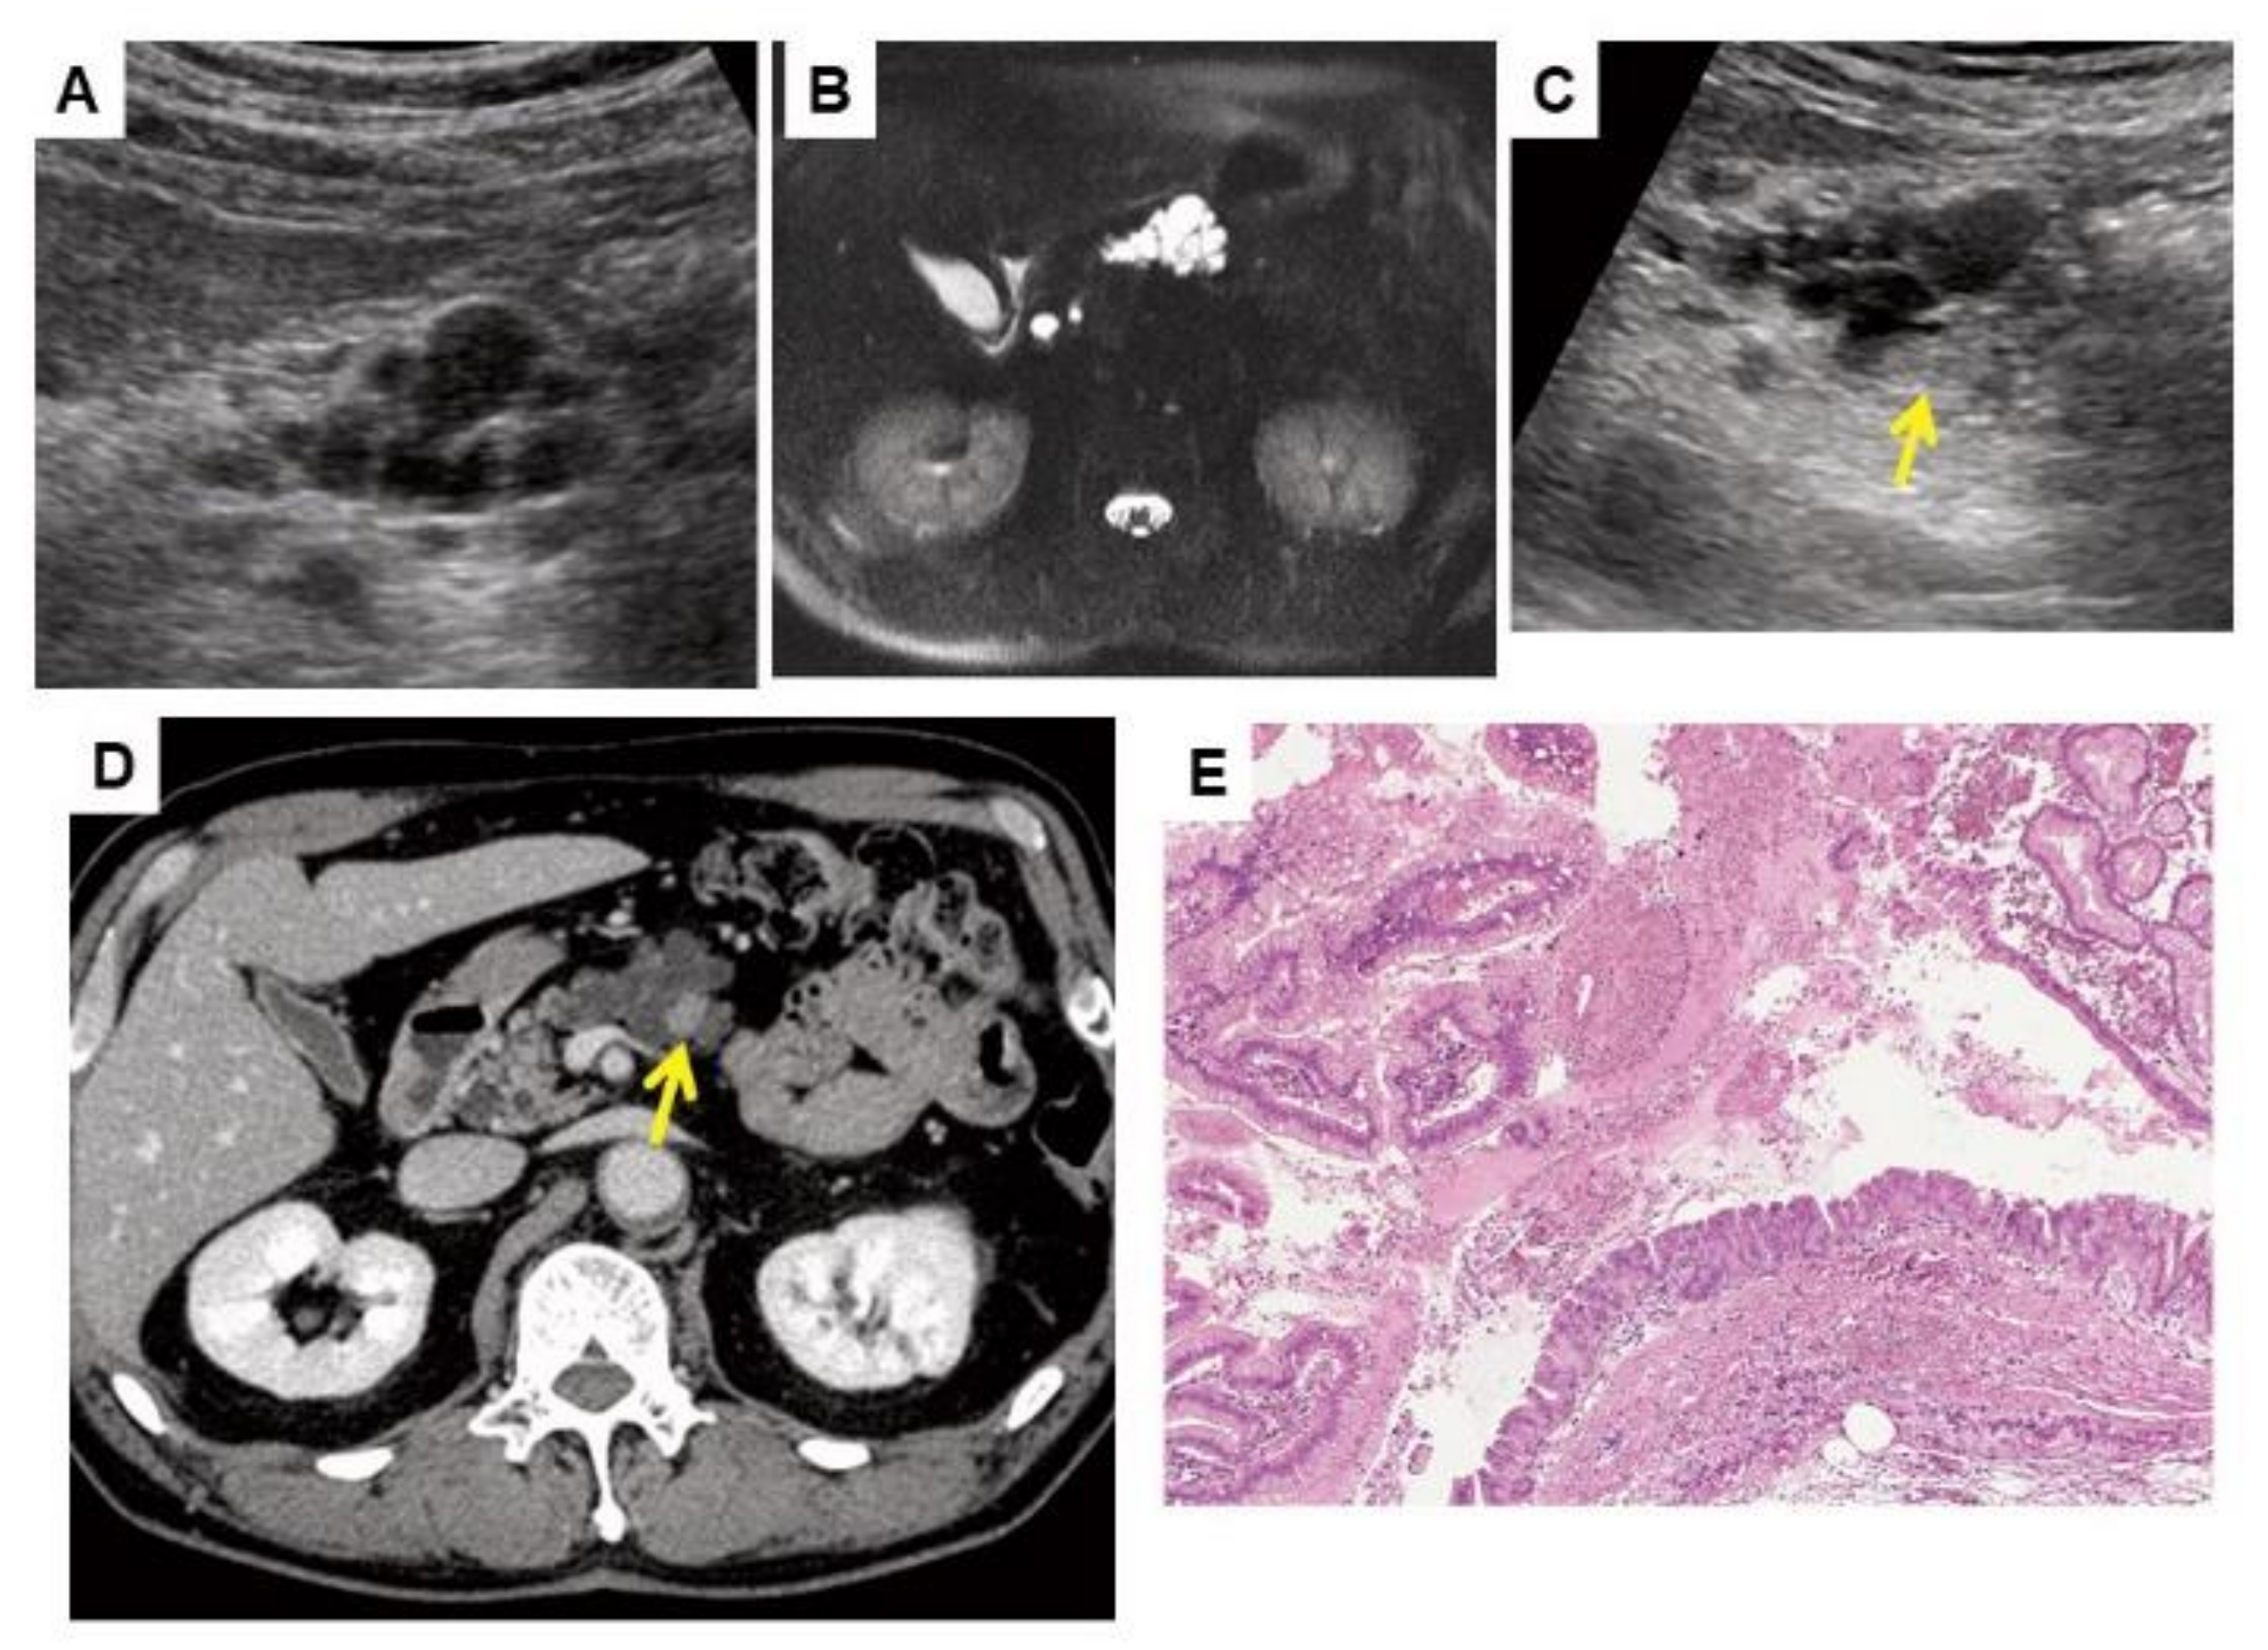

- Fukuda, J.; Tanaka, S.; Ishida, N.; Ioka, T.; Ikezawa, K.; Takakura, R.; Nakao, M.; Ohkawa, K.; Katayama, K.; Nagata, S. A case of stage IA pancreatic ductal adenocarcinoma accompanied with focal pancreatitis demonstrated by contrast-enhanced ultrasonography. J. Med. Ultrason. 2018, 45, 617–622. [Google Scholar] [CrossRef] [PubMed]